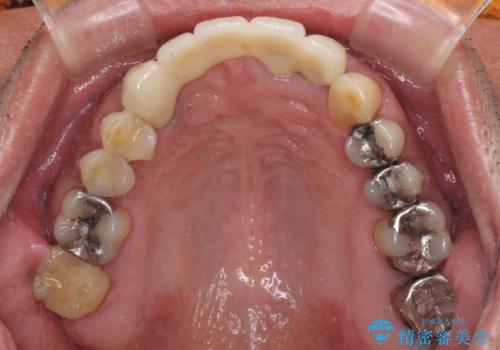

- 前歯のブリッジのせいで話しにくく、金属の縁などが露出して見栄えが悪いので、作り直したいとのことで来院された患者様です。

土台となる歯は根管治療の結果が良好ではないため、根管治療からやり直しをした後、オールセラミックブリッジにて補綴することとしました。

露出していた歯根や金属の縁が見えてしまい、人前で話すときの目線が気になっていらっしゃいましたが、歯肉の位置に縁を合わせてことで自然な仕上がりとなりました。

露出していた歯根が覆われるため、歯冠が長く見えてしまうことが懸念されましたが特に気になることはなく、患者様には大変満足していただきました。